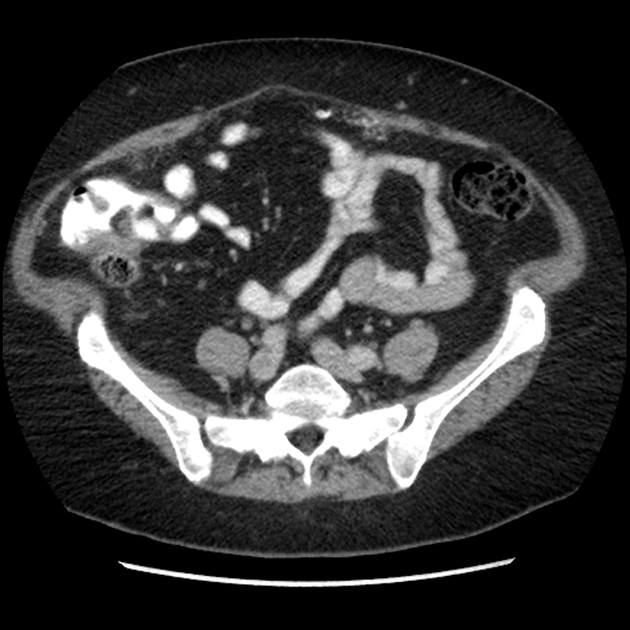

Di căn phúc mạc

Di căn phúc mạc - Ảnh 4

» Thông tin: Nữ giới – 60 tuổi.

» Lâm sàng: Đau mạn sườn phải / Tiền sử buồng trứng.